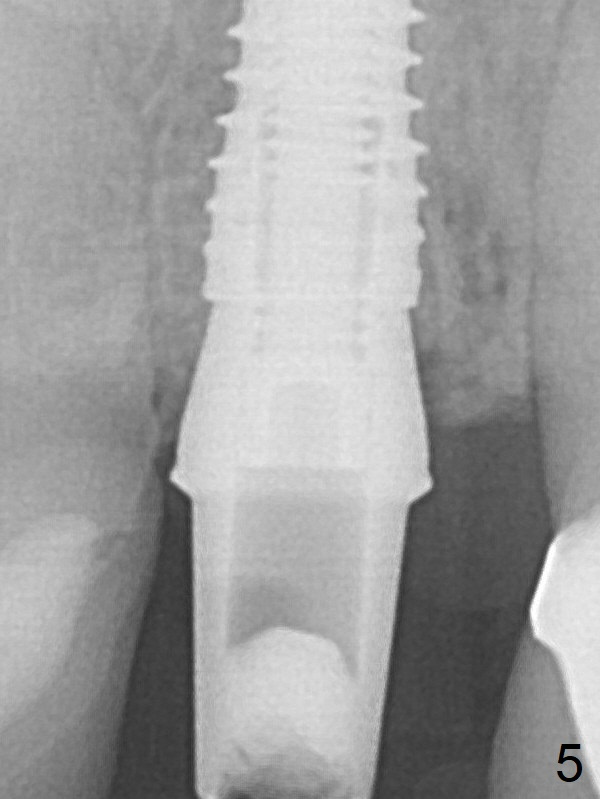

A 3.8x16 mm implant is placed (Fig.4 (with 2 mm buccal gap)) at the level as planned (Fig.2). Insertion torque is acceptable. After placing a 4.5x5(3) mm gold-coated abutment and allograft (Fig.5), an immediate provisional is fabricated (the existing crown is lost). The patient is pleased with the quick, painless procedure.